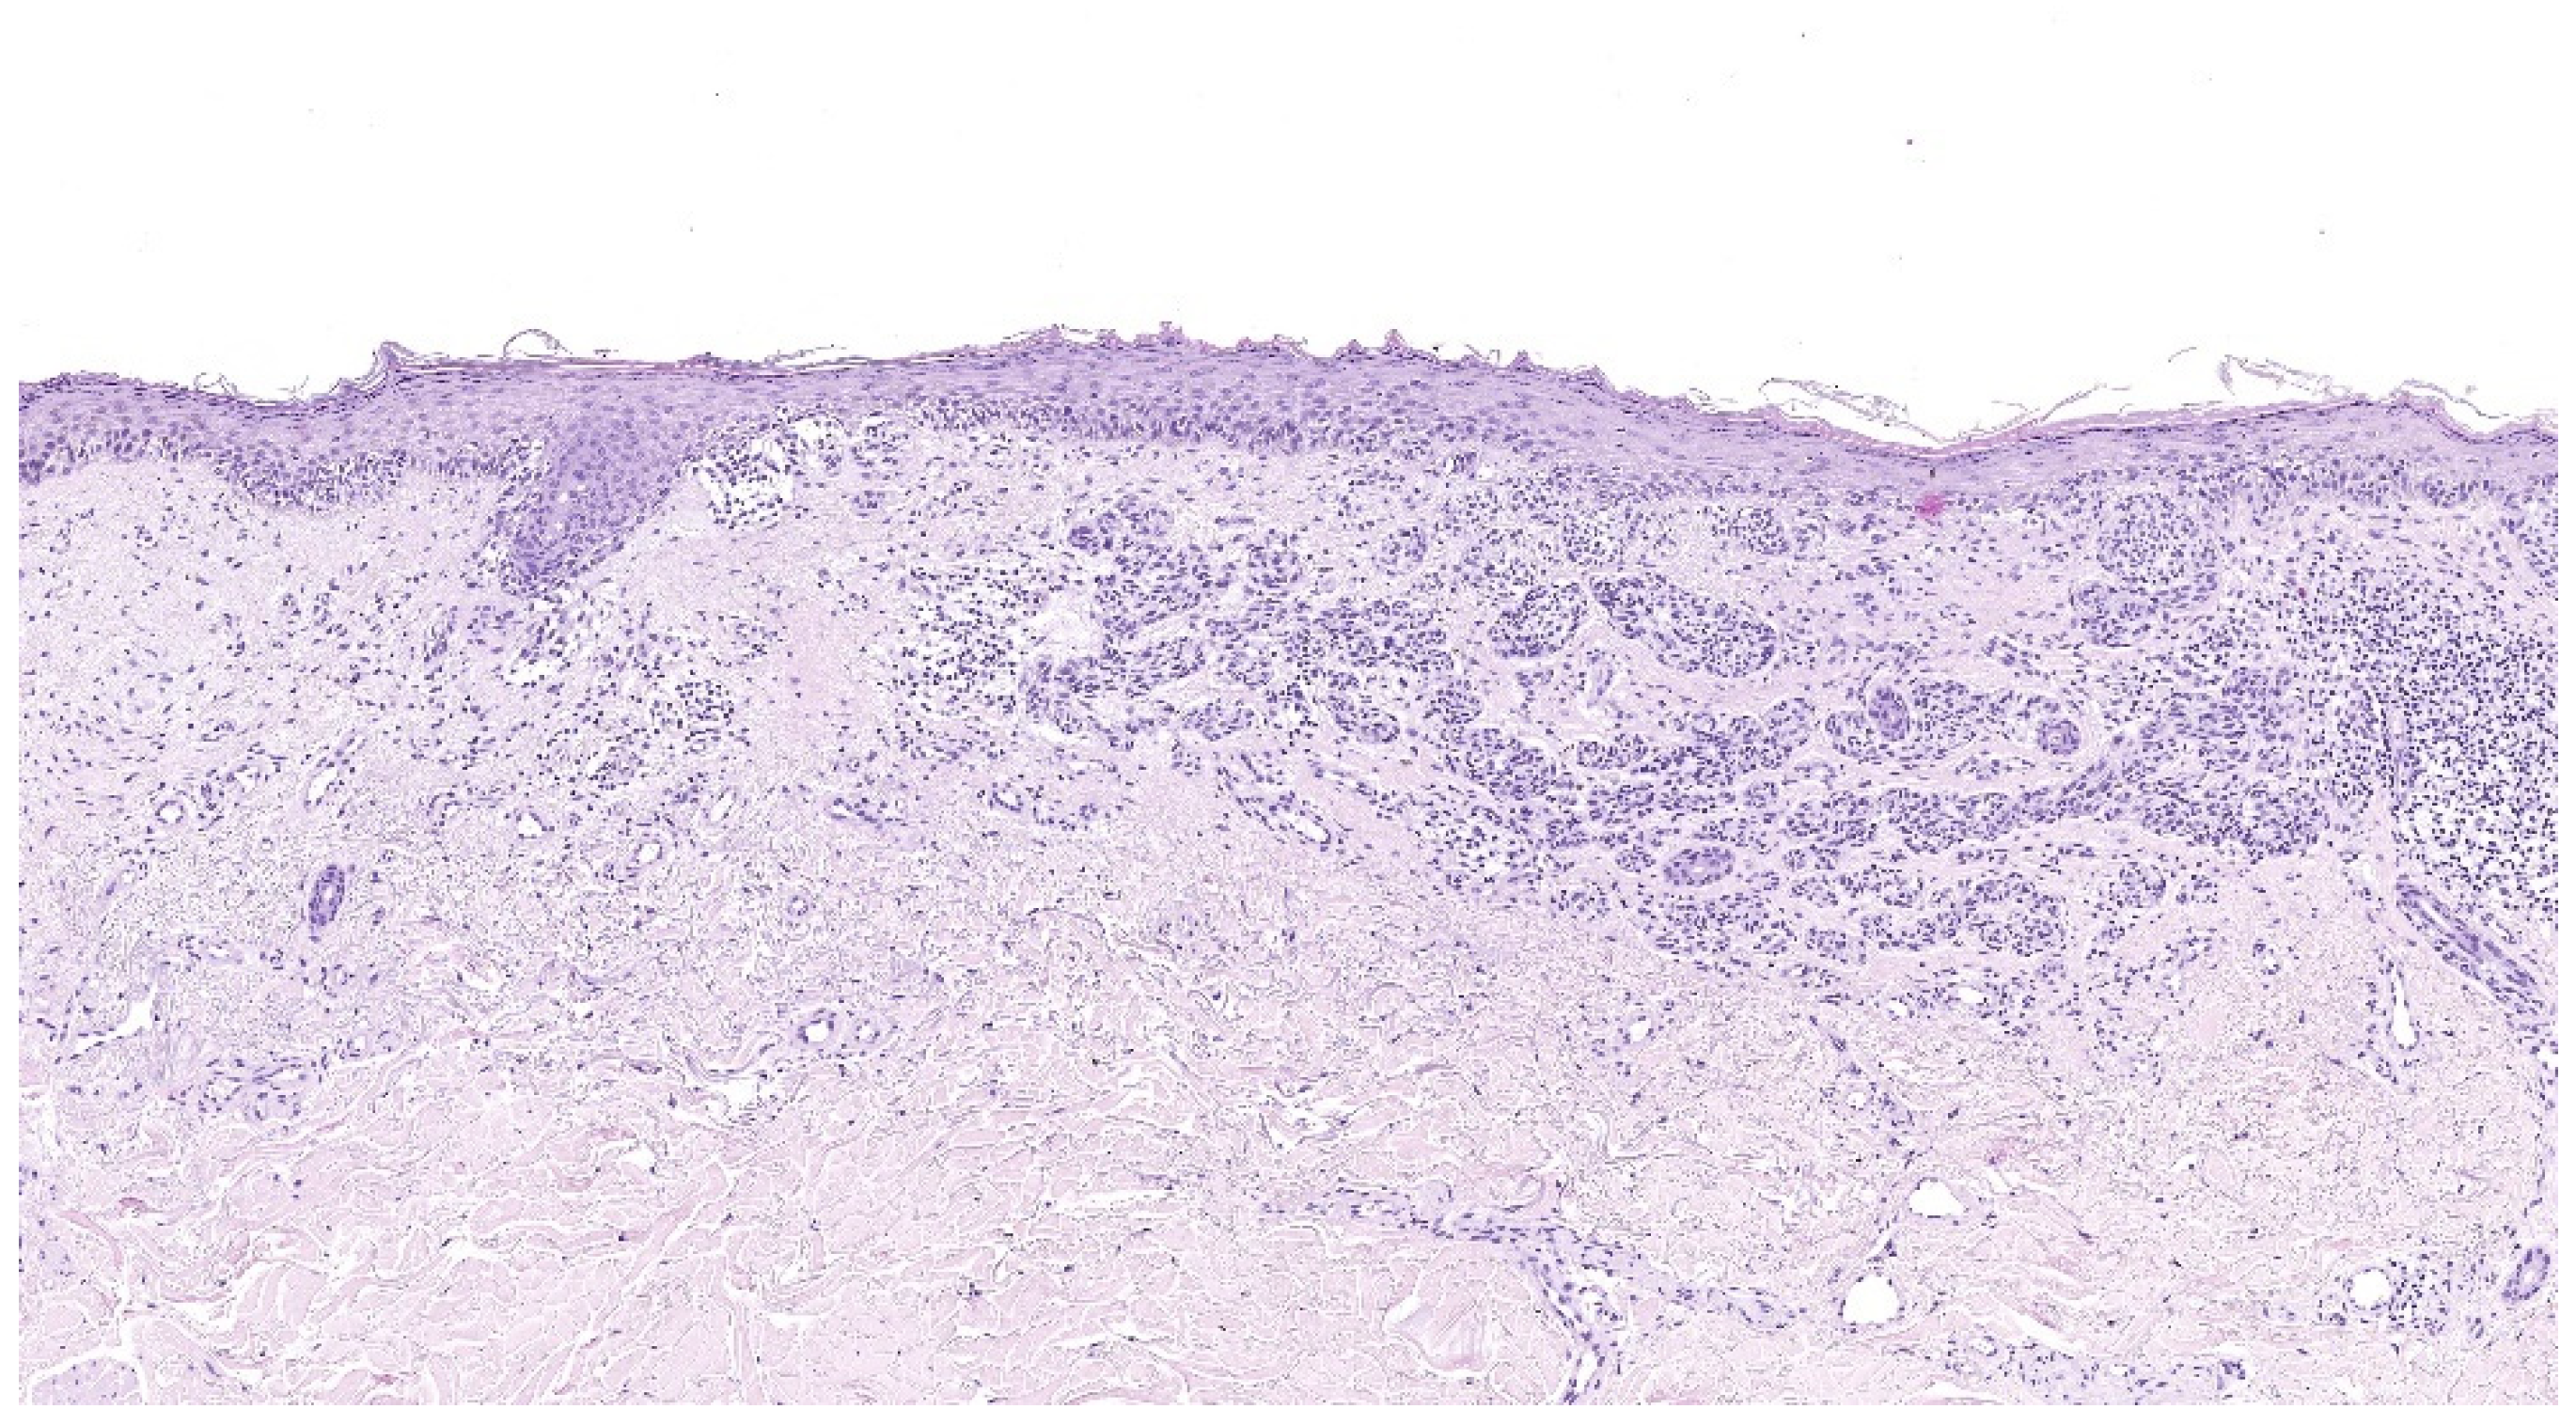

4.2. Lentigo Maligna Melanoma